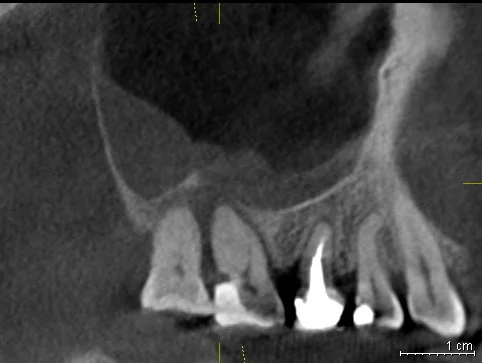

Давайте сравним снимки зубов, сделанные при помощи визиографа (слева), и при помощи компьютерной томографии (справа).

Как говорится, ощутите разницу. КТ - гораздо более точная и своевременная диагностика.

Воссоздавая орган (зуб) или даже совокупность органов, необходимо предельно точно знать исходную ситуацию. Корни зубов, каналы зубов, крупные сосудисто-нервные пучки, идущие внутри костной ткани, верхнечелюстная пазуха во всех подробностях и т.д. - в неискаженном виде все это можно увидеть только на компьютерной томограмме. Стоит ли говорить, что все эти структуры важны для имплантации, так как могут быть легко поврежденфы в ходе операции.